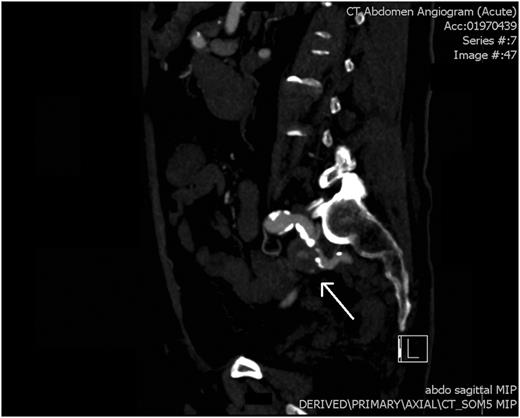

CT angiogram: a saggital view showing pseudoaneurysm of the left internal iliac artery (white arrow).

An arterial phase CT abdomen with IV contrast was performed. This revealed a contrast blush within the descending colon closely associated with an aneurysm of the internal iliac artery. The possibility of an arterial fistula to the colon was raised, and a vascular surgery consult was sought. Angiography confirmed a false aneurysm arising from the proximal aspect of the left internal iliac artery along its medial and inferior wall. Endovascular coil embolization was performed with occlusion of the vessel at the level of the aneurysm.

This patient had an isolated pseudoaneurysm of the internal iliac artery resulting in an arterio-colic fistula (Fig. 1). Isolated aneurysms of the internal iliac artery themselves are a rare phenomenon, estimated to account for only 0.3–0.4% of all intra-abdominal aneurysms. Forty per cent of patients with isolated internal iliac aneurysms will present with a rupture, with mortality estimated to exceed 50% in such patient groups [3].